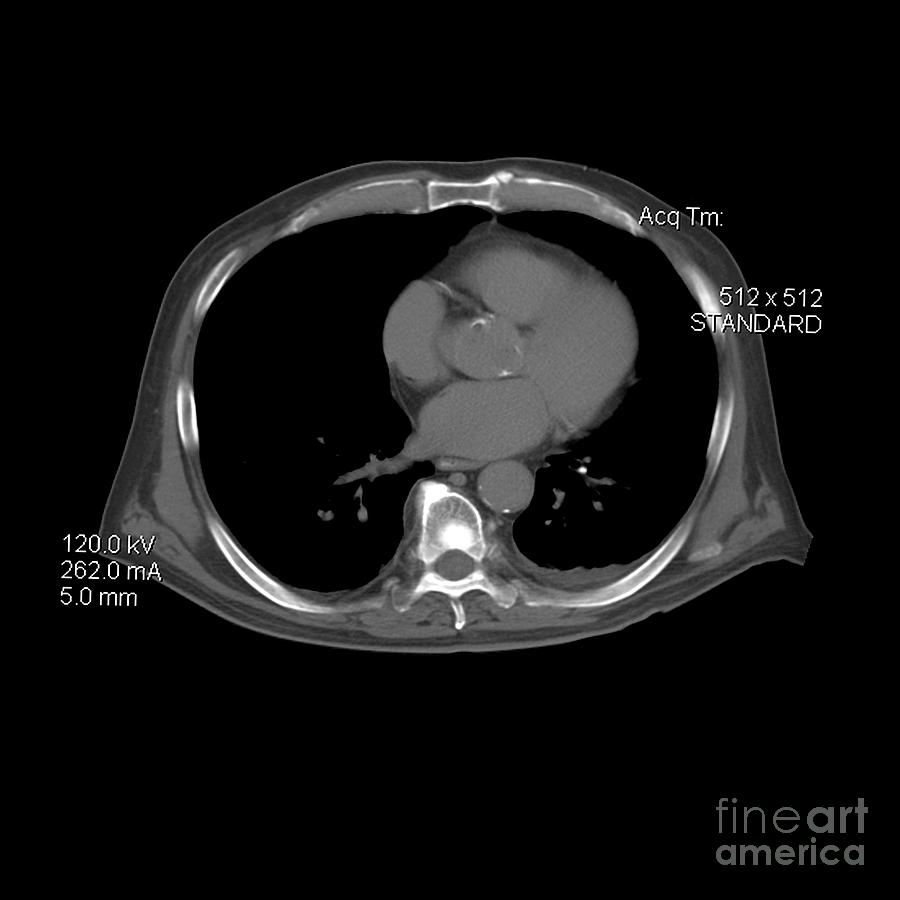

Ct Prostate Cancer Photograph by Medical Body Scans

Ct Prostate Cancer Photograph by Medical Body Scans

Prostate cancer: CT findings | Eurorad